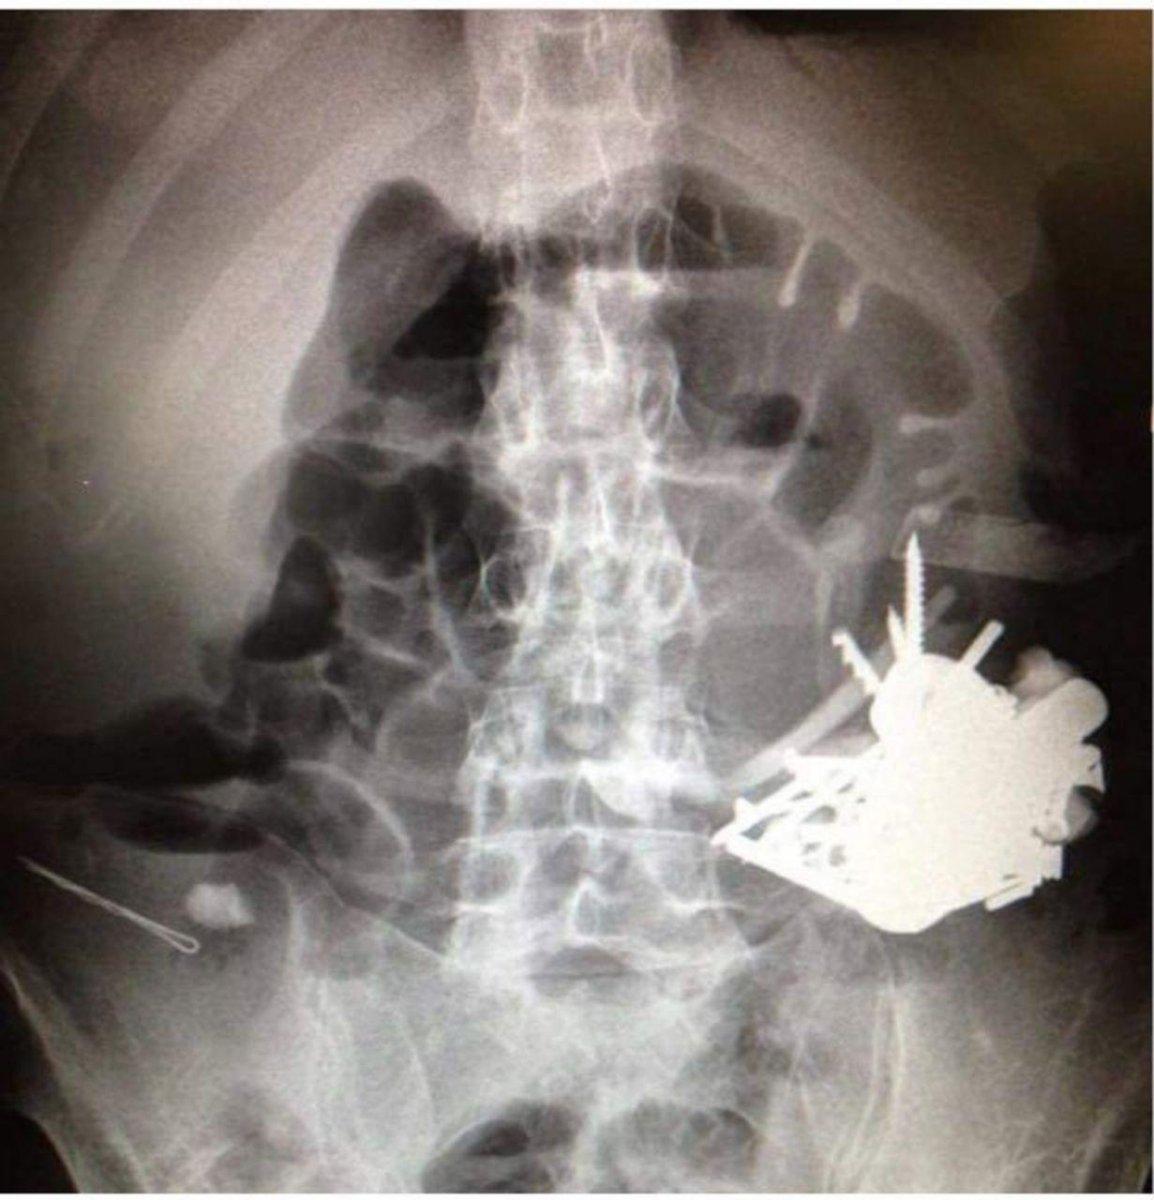

Klaipeda Üniversite Hastanesi'nde röntgeni çekilen adamın midesinde bazıları 10 santim olan metal parçaları görüldü.

Talihsiz adam hemen ameliyata alınırken, operasyonu yöneten cerrah Sarunas Dailidenas, “Üç saatlik operasyon sırasında, hastanın midesindeki tüm yabancı cisimler çıkarıldı.” dedi.